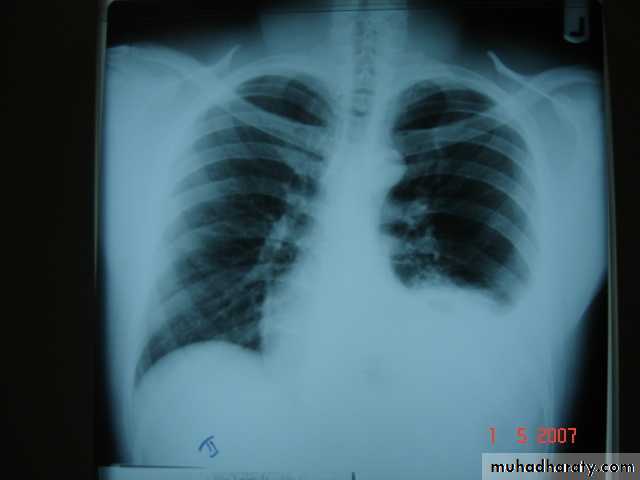

• Bronchiectasis

• Is a persistent abnormal dilatation of the bronchi generally beyond the sub segmental level , generally classified as three types cylindrical , varicose & saccular . The left lower lobe is more commonly involved then the right lower lobe .• Aetiology :-

• It includes (Bronchiectasis , situs inversus ,sinusitis ,sperms hypo motility ) .It represents genetic disorder with abnormal ciliary motility so impaired clearance of sputum with the resultant bronchiectasis .• Clinical manifestation :-The onset is mostly in childhood whereas symptoms generally appear in the second or third decade of life .The disease is more common in females .Major symptom cough with the production of purulent sputum with fetor oris .50% of the patients presented with haemoptysis .Others present with repeated RT infection .,others develop osteo arthropathy & finger clubbing which will resolve with treatment .

• Diagnosis :-

• 1-History chronic cough with purulent sputum.

• 2-Plain CXR may shows prominent vascular marking .

• 3-Bronchoscopy to diagnose obstructive lesion & to obtain bronchial wash for C&S test .

• 4-Bronchography through giving radio opaque dye through the bronchoscope & into bronchial tree ,now replaced completely by CT.

• 5-Chest CT is the single non invasive tool for both diagnosing &assessing the severity of the disease .